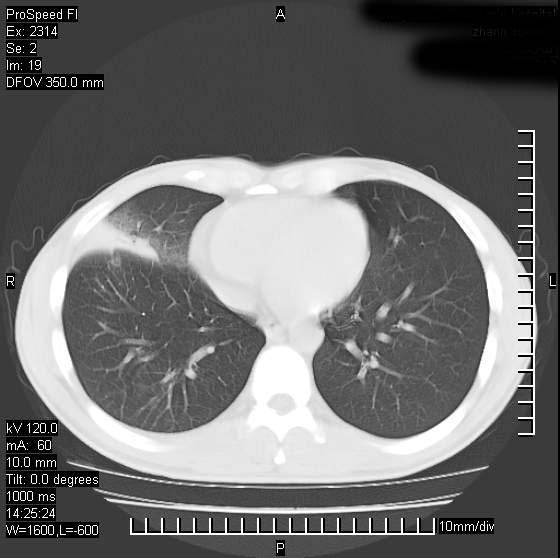

男性,再生障碍性贫血,入院前发热10天,最高40c,右侧胸痛,外院ct示右上,中肺边缘模糊的球性影(就是我现在图中标示的范围),考虑炎症,在我院使用头孢呋辛,洛美沙星10天,高烧消退,自感下午稍有发热,但今天ct示右上,中肺病灶明显扩大,还是考虑炎症,看其中的球型影是否霉菌感染??,是否能排除结核?

右肺中叶外侧段病变,上缘界限不清,下缘锐利,以段性发病为主,内见巨大空洞及空洞内容物,结合病史首先考虑:化脓性肺炎。不除外霉菌感染!

片状高密度影内见空洞影,内可见球形软组织密度影,并有新月征,考虑霉菌感染.

支持右肺上叶、中叶外侧段节段性肺炎伴脓肿形成。